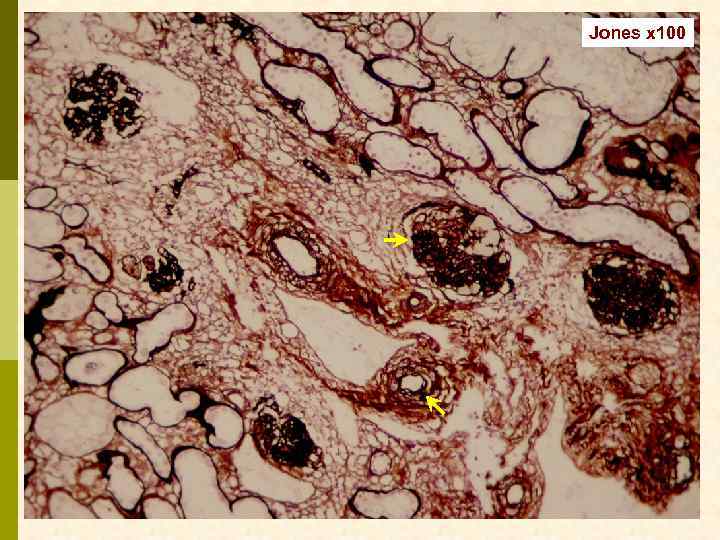

Б. Клинический случай № 21631 Александр К. , 1972 г. рожд. В 1999 г. выявлен гепатит С, в 2003 г. – ВИЧ. С июня 2006 г. – отеки, быстрое развитие анасарки. Почки по УЗИ 13 7 см. Протеинурия 9, 6 г/сут, креатинин 0, 19 мм/л, холестерин 18 мм/л. Обнаружен Ig. M-криоглобулин. 02. 11. 2006 - диагностическая нефробиопсия.

PAS x 100

Masson x 100

Masson x 100

Jones x 100

Jones x 100

PAS x 400

PAS x 400

Jones x 400

Jones x 400

Masson x 400

Masson x 400

Masson x 400

Иммунофлюоресцентное исследование: p Клубочки: Ig. G (2+), Ig. M (3+), C 3 (2+), kappa (3+), lambda (1 -2+) - диффузная, субэндотелиальная и интракапиллярная, крупно-гранулярная экспрессия; p Стенки артериол: C 3 (2+); p Цилиндры: Ig. G (2+), Ig. A (3+), Ig. M (2+), C 3 (3+), kappa (3+), lambda (2+); p Реабсорбированные белковые капли: kappa (3+).

Предварительное гистологическое заключение: p Мембрано-пролиферативный, HCV-ассоциированный, криоглобулинемический(? ) гломерулонефрит с полным склерозом 47% клубочков, сегментарным склерозом 22% клубочков и формированием полулуний в 15% клубочков; p диффузно-очаговый выраженный острый канальцевый некроз; p выраженный артерио-артериолосклероз. Примечание: Криоглобулинемическая природа поражения будет уточняться при ЭМ-исследовании.

Заключение p Мембрано-пролиферативный гломерулонефрит, криоглобулинемический, ВИЧ-ассоциированный, на фоне гепатита С